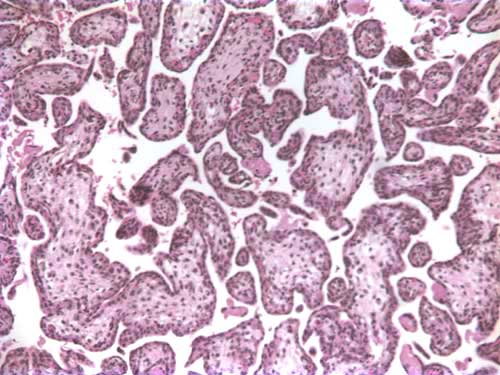

Figure 3: H & E stain of a partial

hydatidiform mole (different case);

note the large hydropic villus with a

trophoblastic inclusion surrounded

by smaller villi

Phenotypically, diandric triploidy conceptuses are associated with an enlarged placenta that is histology consistent with a partial hydatidiform mole (see attached figure 3). In the case described above, the triploid conceptuses occurred in subsequent pregnancies, and neither showed evidence of a partial hydatidiform mole suggesting that the triploidy was attributable to maternal origin. A suggested maternal mechanism resulting in triploidy is nondisjunction in meiosis I or meiosis II of oogenesis.